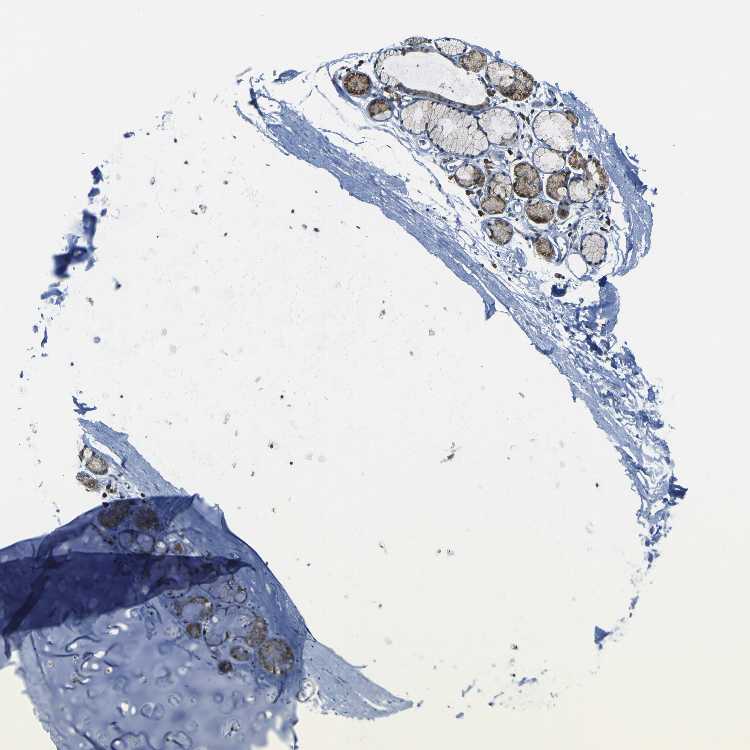

ADIPOSE TISSUE - Antibody stainingi

Antibody staining in the annotated cell types in the current human tissue is reported as not detected, low, medium, or high, based on conventional immunohistochemistry profiling in selected tissues. This score is based on the combination of the staining intensity and fraction of stained cells.

Each image is clickable and will lead to virtual microscopy that enables deeper exploration of all samples and also displays staining intensity scores, fraction scores and subcellular localization as well as patient and tissue information for each sample.

Antibody HPA011088Antibody HPA012123Antibody CAB037128Antibody CAB037288

Adipocytes LowNot detectedLowLow